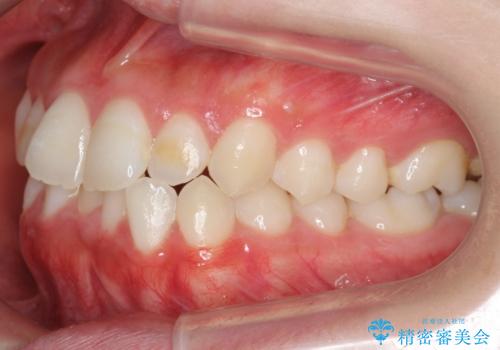

下の歯のがたつき 上より気になる

- 前歯のがたつきが気になって来院。

下の歯のがたつきが上よりも多い状態でした。

下の前歯は上の歯の内側にあるため、外に並べることができないため、上ほど簡単ではありません。

すき間をしっかりとって並べる必要があります。

今回は、下の歯を健康に支障が出ない範囲でわずかに削合し、並べるようにしました。(ディスキングといいます)

前歯のがたつきもしっかり治り、喜んでいただけました。

下の親知らずは虫歯になっていたため矯正前に抜歯しています。